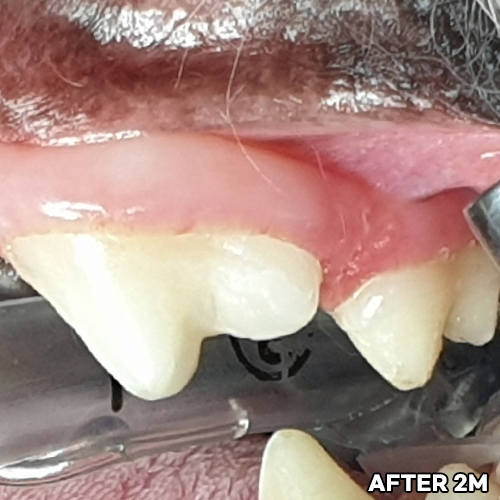

[강아지잇몸뼈 치료 후 2달 경과]

[강아지잇몸뼈 재생치료 하고 재생된 자기 잇몸뼈]